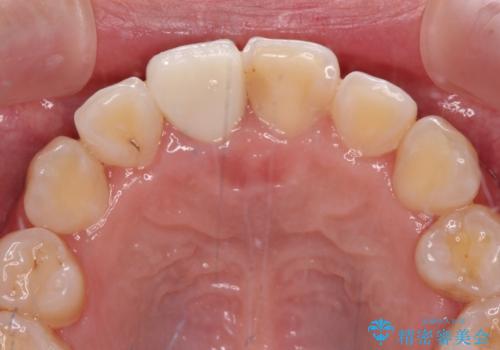

虫歯と抜いたままの奥歯とデコボコの前歯 総合歯科治療

- 放置した虫歯や抜いたままの奥歯、前歯のデコボコを気にして来院された患者様です。

口元の突出感は少なく、下顎の叢生は軽微なものであったので、叢生の強い上顎左右の小臼歯を1本ずつ抜歯し、ワイヤー装置にて矯正治療を行うこととしました。

矯正治療を行う前に、根管治療の必要な上顎前歯と下顎大臼歯の根管治療を行い、矯正治療の途中で下顎の欠損部にインプラント埋入することとし、矯正治療後に補綴治療を行うこととしました。

矯正治療中にインプラント埋入を行うなど、余計な時間や無駄のない治療を行うことができました。